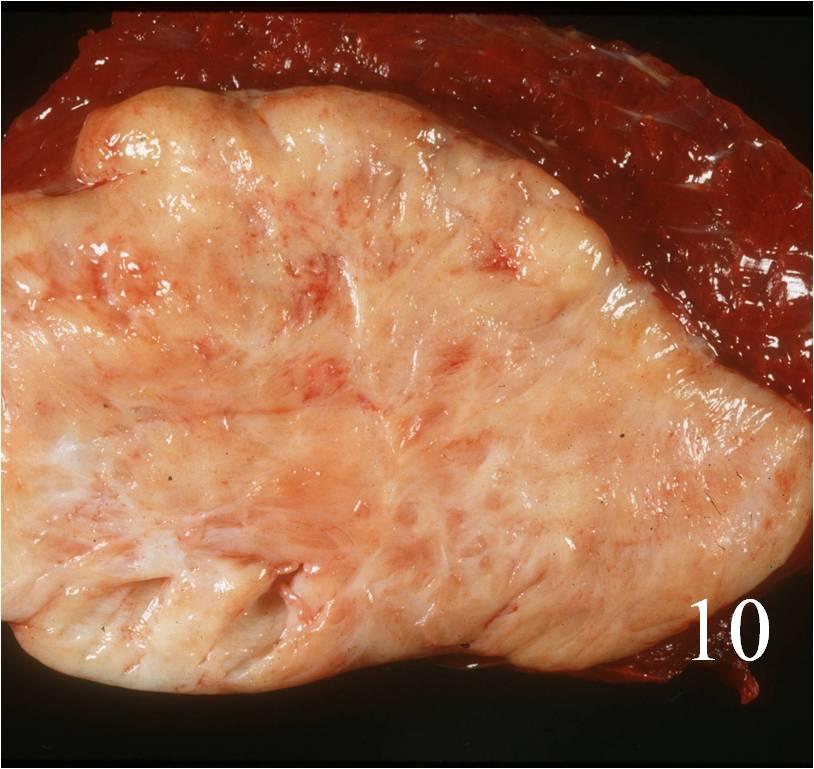

Gross

- Fleshy, solid and well circumscribed with a pseudocapsule (Fig. 10)

- Hemorrhage and necrosis evident